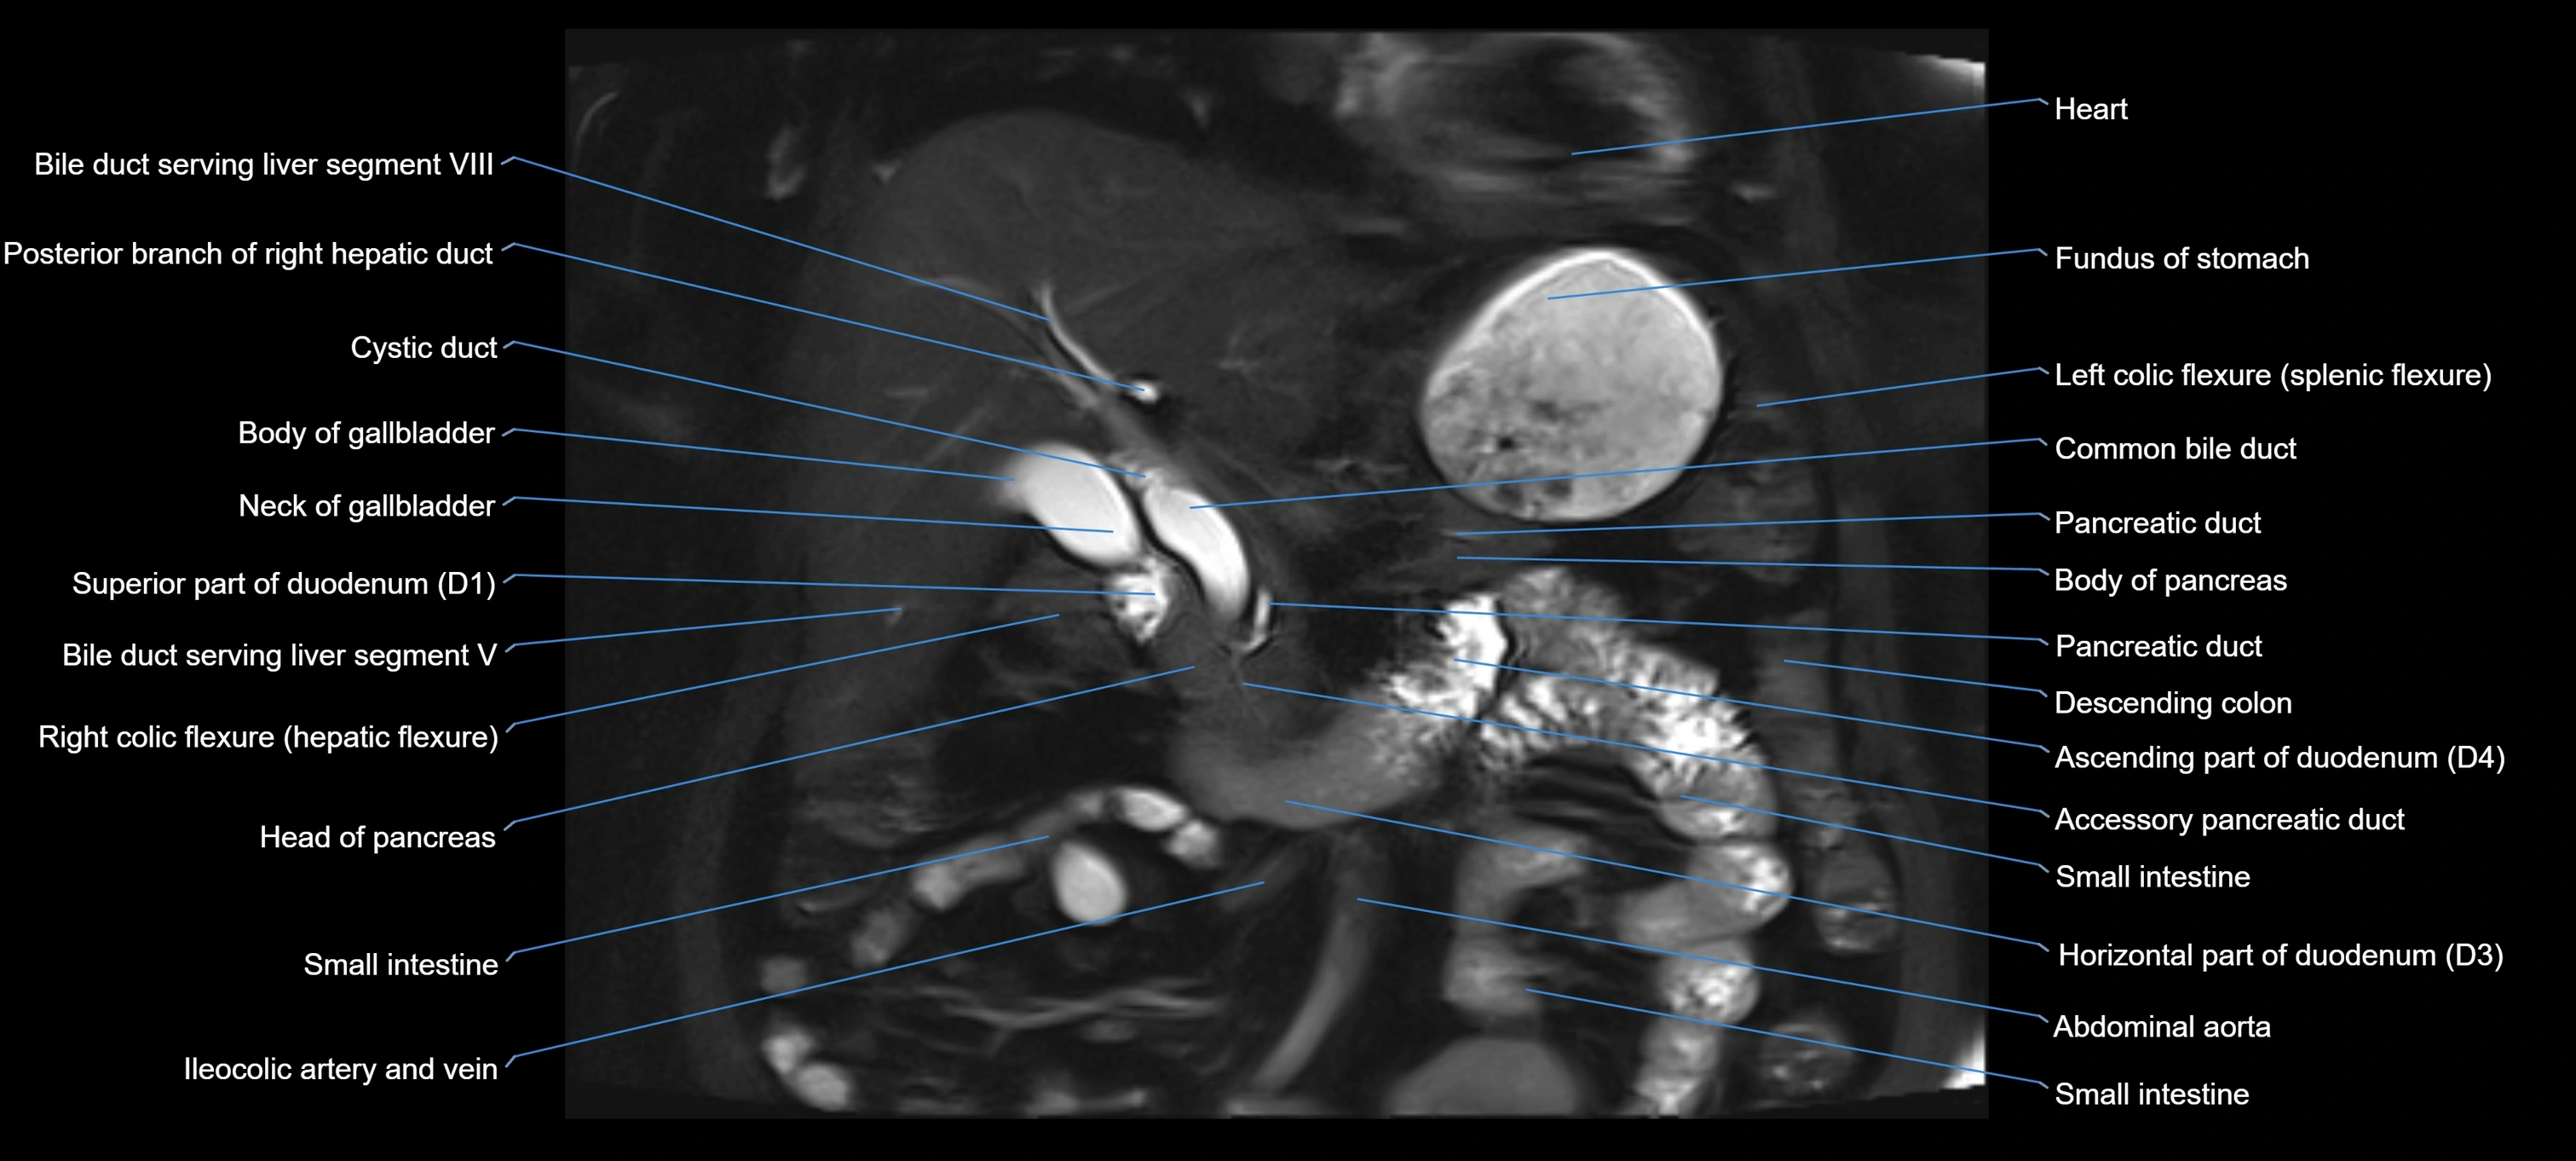

MRI Appearance

T1-weighted images:

• Not typically visualized unless dilated; appears as low signal tubular structure if seen

• Surrounding pancreatic parenchyma shows intermediate signal

T2-weighted images:

• Duct fluid appears bright

• Accessory duct seen as a fine high-signal tubular structure in pancreatic head

STIR (Short Tau Inversion Recovery):

• Duct fluid remains bright

• Surrounding fat suppressed, improving duct conspicuity

T1 Fat-Sat Post-Contrast:

• Normal duct does not enhance

• Surrounding inflammatory or neoplastic changes may enhance

T2 Fat-Saturated HASTE (single-shot):

• Accessory duct: bright, thin linear structure in pancreatic head

• Stones, strictures, or air bubbles appear as dark filling defects

• Excellent for rapid evaluation of duct patency

T2 TSE Fat-Saturated 3D (MRCP sequence):

• Duct visualized as a continuous bright tubular structure joining or parallel to the main pancreatic duct

• Allows 3D reconstruction of ductal anatomy and variants

• Excellent for diagnosis of pancreas divisum

Thick-slab T2 Fat-Saturated HASTE:

• Shows the accessory duct as part of the biliary–pancreatic system in a projectional image

• Highlights communication with main pancreatic duct and opening into the minor papilla

• Filling defects (stones, strictures) seen as dark spots within bright fluid

MRI image

image